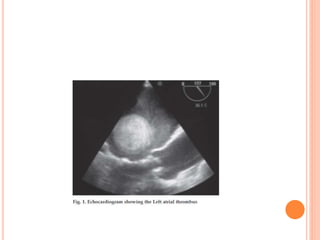

 The thrombus in the left atrium can be classified as

(Manjunath et al.) -

 Ia (thrombus confined to LAA)

 Ib (thrombus in LAA and protruding into LA cavity)

 IIa (attached to LA roof but above the plane of fossa ovalis)

 IIb (reaching below plane of fossa ovalis)

 III (attached to interatrial septum)

 IV (mobile with attachment to roof or lateral wall)

 V (ball valve thrombus)

CLASSIFICATION  The thrombusin the left atrium can be classified as (Manjunath et al.) -  Ia (thrombus confined to LAA)  Ib (thrombus in LAA and protruding into LA cavity)  IIa (attached to LA roof but above the plane of fossa ovalis)  IIb (reaching below plane of fossa ovalis)  III (attached to interatrial septum)  IV (mobile with attachment to roof or lateral wall)  V (ball valve thrombus)